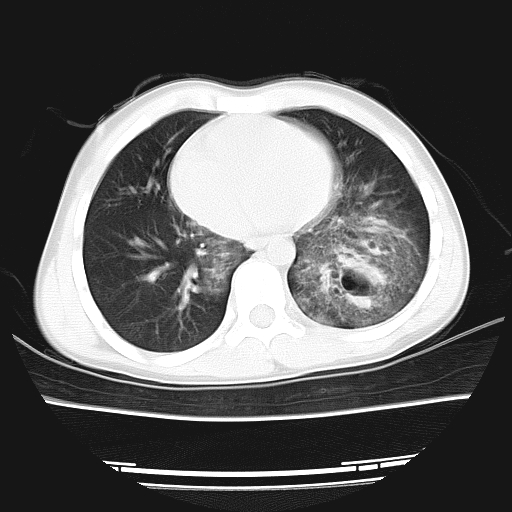

11岁男孩,二楼坠落伤。胸部体症不明星,上腹部痛,腹部ct正常。大家看看,过两天再传复查的片子。

双侧创伤性湿肺,左侧明显并肺大炮。

双侧创伤性湿肺,左侧明显并肺大泡

双侧创伤性湿肺,左侧血肿形成。

双侧创伤性湿肺,左肺挫裂伤,不除外肺囊肿,建议复查.

双侧创伤性湿肺伴左下肺叶创伤性肺气囊形成

双侧创伤性湿肺,左肺挫裂伤(气血囊肿)。

肺挫裂伤并气血囊肿形成

双侧创伤性湿肺伴左下肺撕裂伤并假囊肿形成